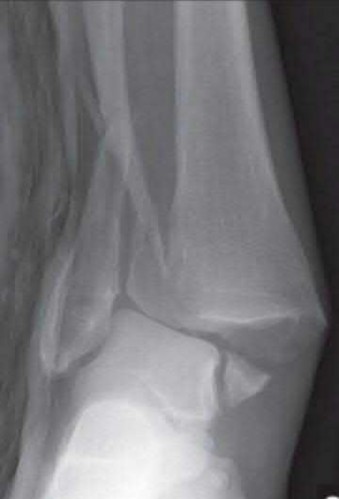

A 25-year-old female is involved in a motor vehicle collision. She presents with the isolated injury seen in Figures A through D. Her leg is swollen but her skin is intact. She has no clinical signs of compartment syndrome. Which of the following treatment options will allow for maintenance of fracture alignment and minimize the risk of soft tissue complications?

The patient presents with a closed distal third metaphyseal-diaphyseal distal tibia fracture with simple intra-articular extension. Immediate intramedullary nailing along with percutaneous fixation of the articular component provides appropriate restoration of length, rotation and alignment and minimizes the risk of wound complication.

Displaced distal third tibia fractures may be associated with simple intraarticular extension. Operative treatment of intra-articular distal tibia fractures has historically been performed with open reduction and internal fixation. Early open reduction and plate fixation of pilon fractures has been associated with high rates of infection and wound complication. In select patterns with simple articular extension, percutaneous screw fixation and medullary nailing may provide appropriate reduction with minimal soft-tissue risk.

Marcus et al. evaluated the outcomes of immediate intramedullary nailing and percutaneous fixation of simple intra-articular distal tibia fractures (AO/OTA 43 C1 and C2). The authors found excellent rates of union and alignment, however caution against broad application of this technique until more rigorous randomized studies can be performed.

Sirkin et al. retrospectively evaluated the results of a staged approach to management of intra-articular distal tibia fractures with temporary bridging external fixation followed by open reduction and internal fixation (ORIF). The authors found decreased rates of wound complication and infection compared with prior studies.

Figures A and B demonstrate a distal third tibial shaft fracture with simple intra-articular extension. The axial and coronal CT cuts in Figures C and D further clarify the articular injury. Illustrations A and B demonstrate a comminuted distal third tibial fracture with simple intra-articular extension. Illustrations C and D are fluoroscopic images of the same injury after intramedullary nailing and percutaneous fixation of the articular component.